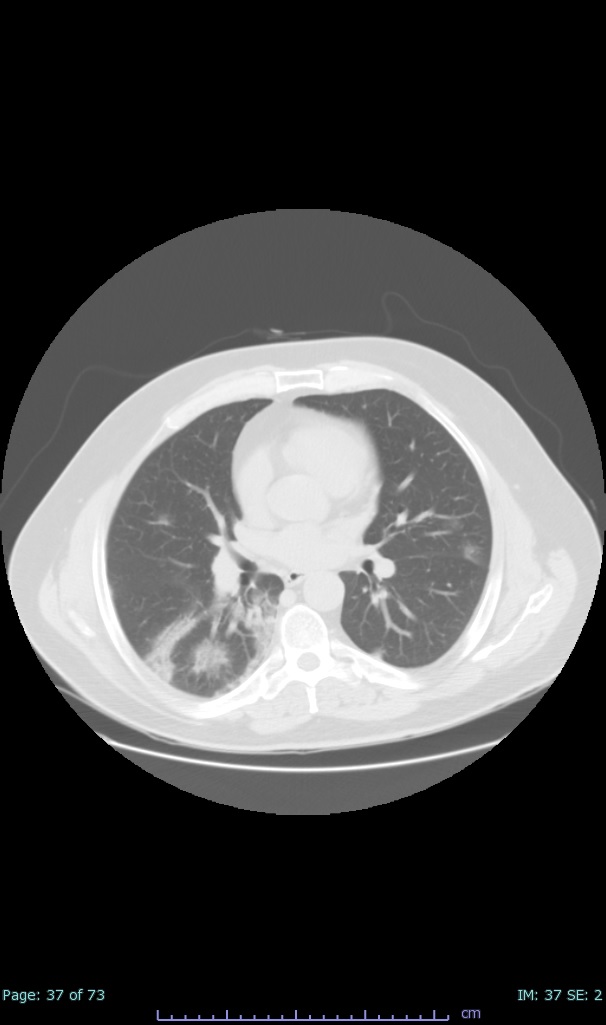

- 100% subpleural involvement, 33% + centrolobular involvement

- 40% even apical/basilar, 27% basilar dom, 5% mid dom. 1/17